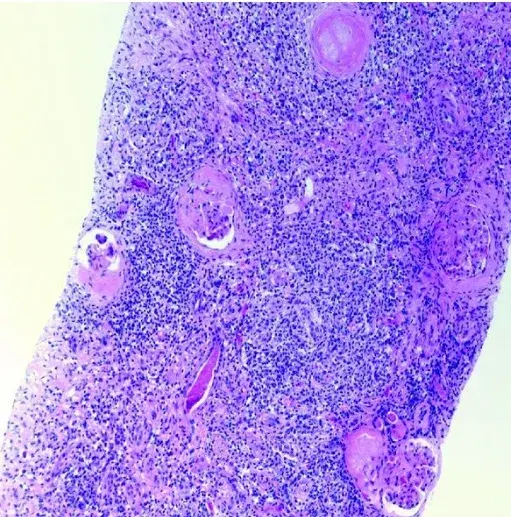

Jovem com hipertensão e massa abdominal